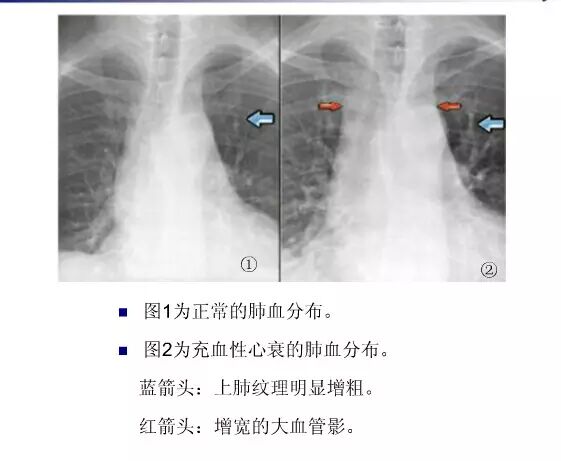

平片如何看心衰